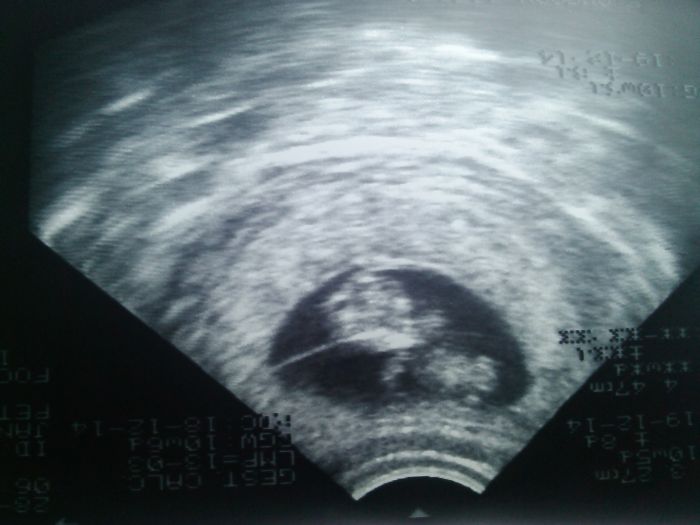

Holky vše je OK.Fazolka všechno dohnala podle MS jsem 10+6tt podle UZ jsem 10+5tt

Konečně mám 1 fotečku.Holky já jsem tak šťastná,že je všechno v pořádku

A tímhle bych Vás s radostí chtěla představit moji krásnou fazolku

[550767] gratuluju k uspesne prohlidce :)) fazolka je krasna ;)

[550767] Gratuluji k uspěšné prohlídce a fotka je nádherná, taky se těším na první fotku, ale ještě sei na ní počkám do půlky června

[550767] Moc gratuluju, prďolka je krásná